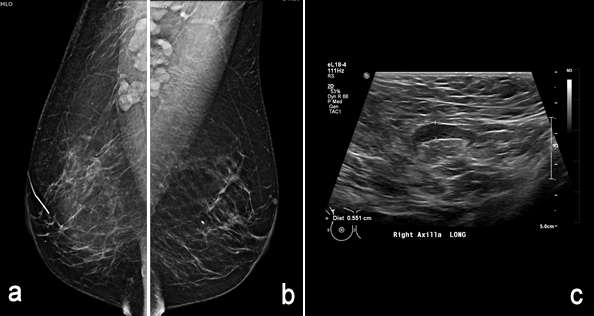

Figure 5, a-c.

The axilla is partially imaging during mammography and axillary lymph nodes are commonly seen. Evaluation of lymph nodes on mammography involves assessment of laterality and lymph node morphology. Benign axillary lymph nodes (figure 1) are oval in shape, typically measuring less than 2 cm, with a preserved fatty hilum which appears as radiolucent notch on mammogram. Increased lymph node size or density can be abnormal, requiring additional evaluation1. In the case of abnormal lymphadenopathy, attention should be made to whether the lymph nodes are unilateral or bilateral as this can help narrow the differential diagnosis1,2.

Ultrasound is the best modality for characterizing lymph nodes allowing for evaluation of shape, cortical thickness and presence or absence of fatty hilum. On ultrasound, normal axillary lymph nodes have an oval or lobulated shape with a preserved fatty hilum and cortical thickness less than 3 mm (figure 2). The echogenic hilum has arterial flow which can be assessed using color doppler imaging.